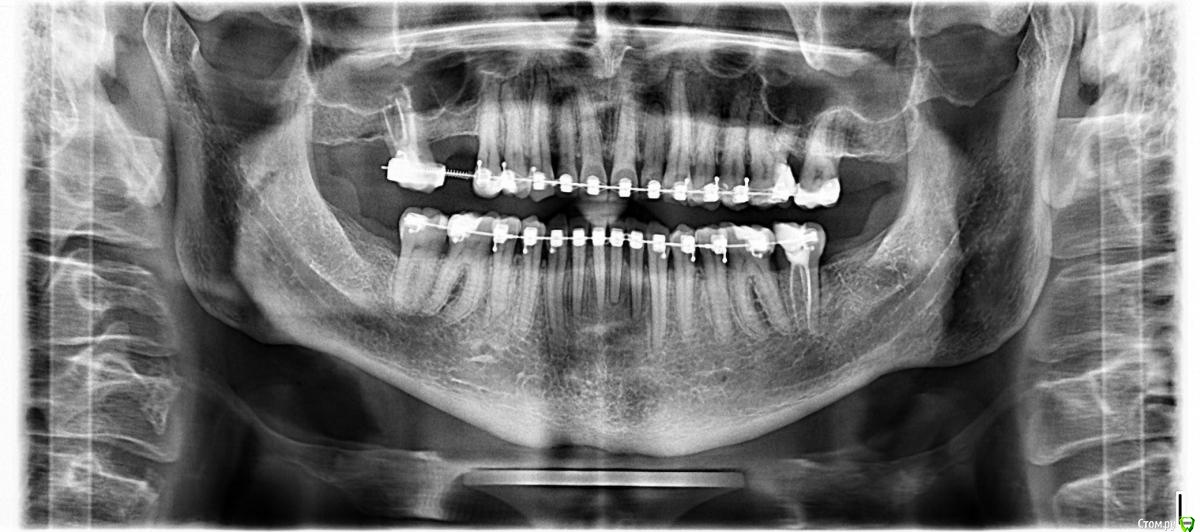

al7777 Опубликовано 18 января, 2021 Автор Поделиться Опубликовано 18 января, 2021 Большое спасибо!Поставили имплант в септу плюс ЗСЛ. 1 Ссылка на комментарий